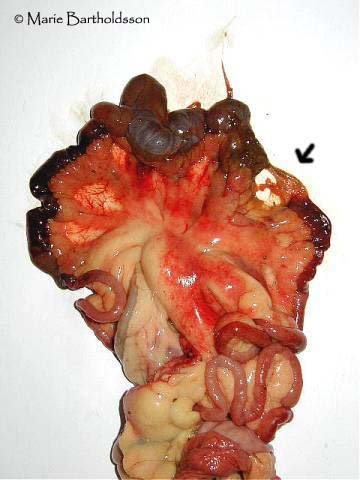

Mingo's ruptured bowel

Mingo died of sepsis caused by a ruptured bowel. He had accidentally ingested some wood chips together with his food. The small intestine had ruptured about 25-50 cm from the rectum and the whole adomen and it's organs (except for the liver) were severely affected by the infection from the intestinal content. In the picture one can see the rupture (arrow) and the distended section following the rupture. The dark portions are from where the intestine has been haemorrhaging.